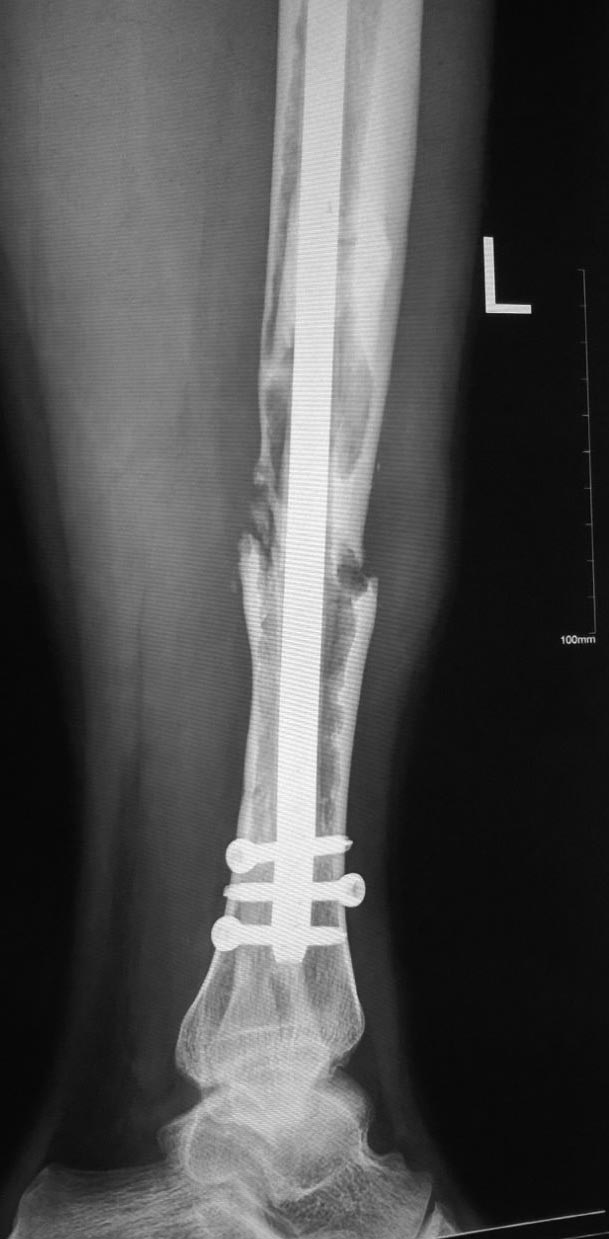

Re: Несращение большеберцовой кости

Виталий Валерьевич, добрый день. Пациент сейчас в другом городе, прислал снимки без проксимального отдела. Боковую проекцию добавлю.